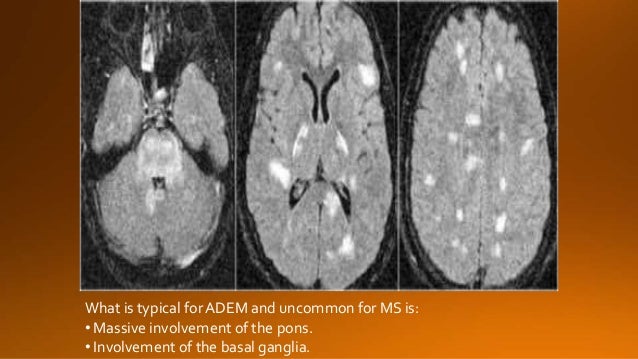

• How can I improve my memory and concentration? How can I improve my memory for studying?➤➤ https://tinyurl.com/brainpill101

Are you sure you want to  Yes  No

Your message goes here